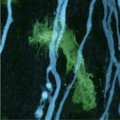

Sitemap > Presse & Kommunikation > Aktuelle Meldungen > Frühe Schäden bei Multipler Sklerose sind umkehrbar > Bei Multipler Sklerose attackieren Immunzellen (grün) die Nervenfasern oder Axone (blau). Die Aufnahme stammt aus dem Rückenmark einer Maus.

Bei Multipler Sklerose attackieren Immunzellen (grün) die Nervenfasern oder Axone (blau). Die Aufnahme stammt aus dem Rückenmark einer Maus.

Copyright: Thomas Misgeld und Martin Kerschensteiner / TUM und LMU